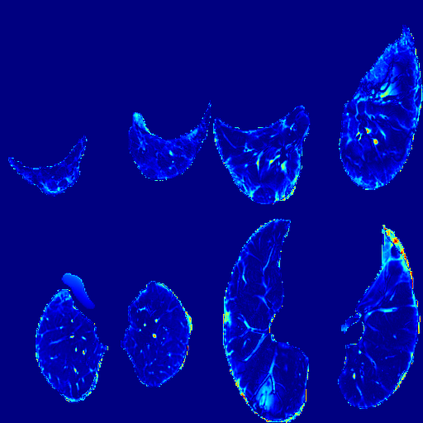

In the field of medical imaging, particularly in tasks related to early disease detection and prognosis, understanding the reasoning behind AI model predictions is imperative for assessing their reliability. Conventional explanation methods encounter challenges in identifying decisive features in medical image classifications, especially when discriminative features are subtle or not immediately evident. To address this limitation, we propose an agent model capable of generating counterfactual images that prompt different decisions when plugged into a black box model. By employing this agent model, we can uncover influential image patterns that impact the black model's final predictions. Through our methodology, we efficiently identify features that influence decisions of the deep black box. We validated our approach in the rigorous domain of medical prognosis tasks, showcasing its efficacy and potential to enhance the reliability of deep learning models in medical image classification compared to existing interpretation methods. The code will be publicly available at https://github.com/ayanglab/DiffExplainer.